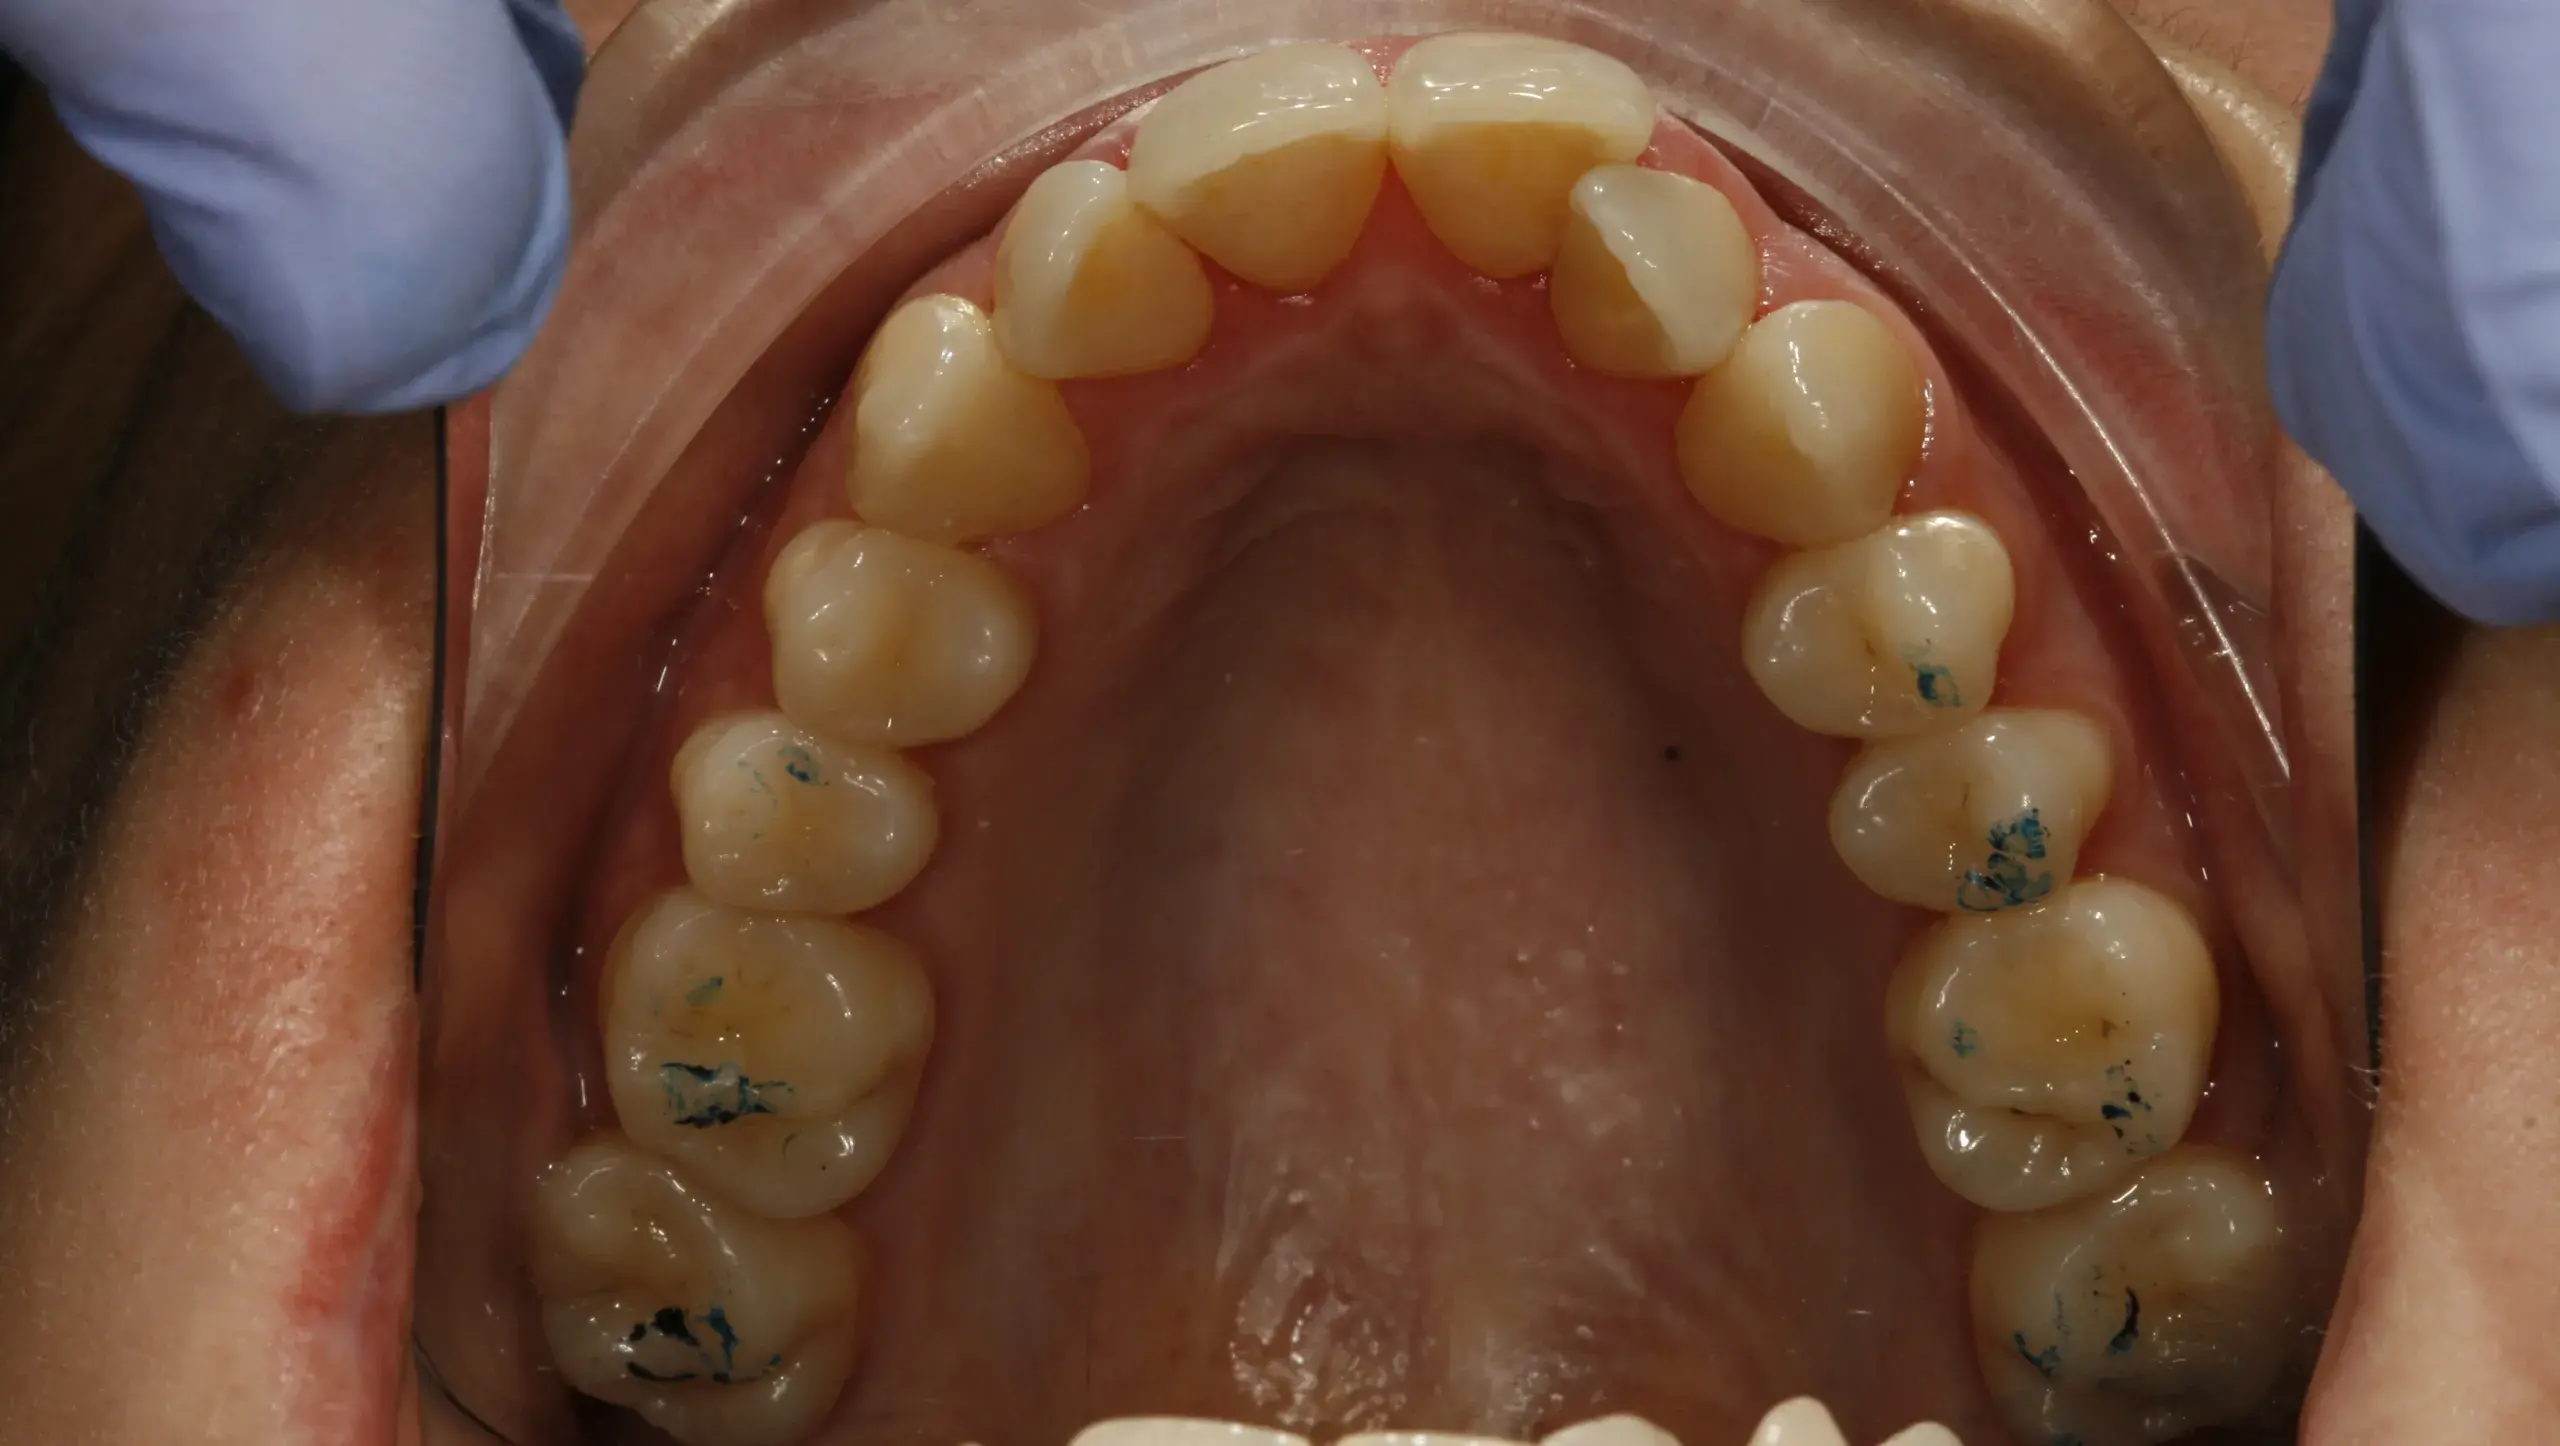

Caso clínico 5: Canino inferior incluido

Caso clínico 5: Canino inferior incluido El diagnóstico principal para este caso fue un canino inferior impactado.Antes de la ortodoncia:Canino impactado:El canino inferior derecho no había erupcionado en su posición…